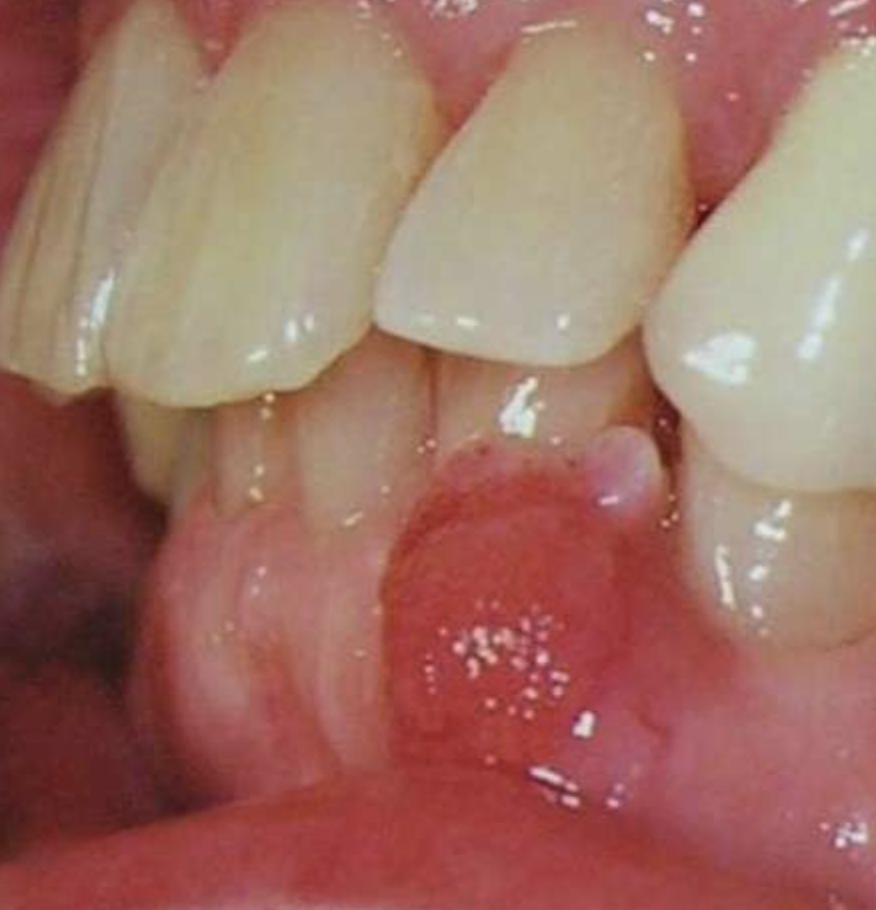

T/F: peripheral ameloblastomas are soft tissue lesions only

true

peripheral ameloblastomas affects max or mand more

mand

peripheral ameloblastomas affect which age group

average age = 52

histopath features of peripheral ameloblastomas

epithelial islands beneath surface epithelium

plexiform and follicular patterns most common

50% show connection to basal layer of surface epithelium

tx options for peripheral ameloblastomas

local excision w/ 15-20% reoccurrence